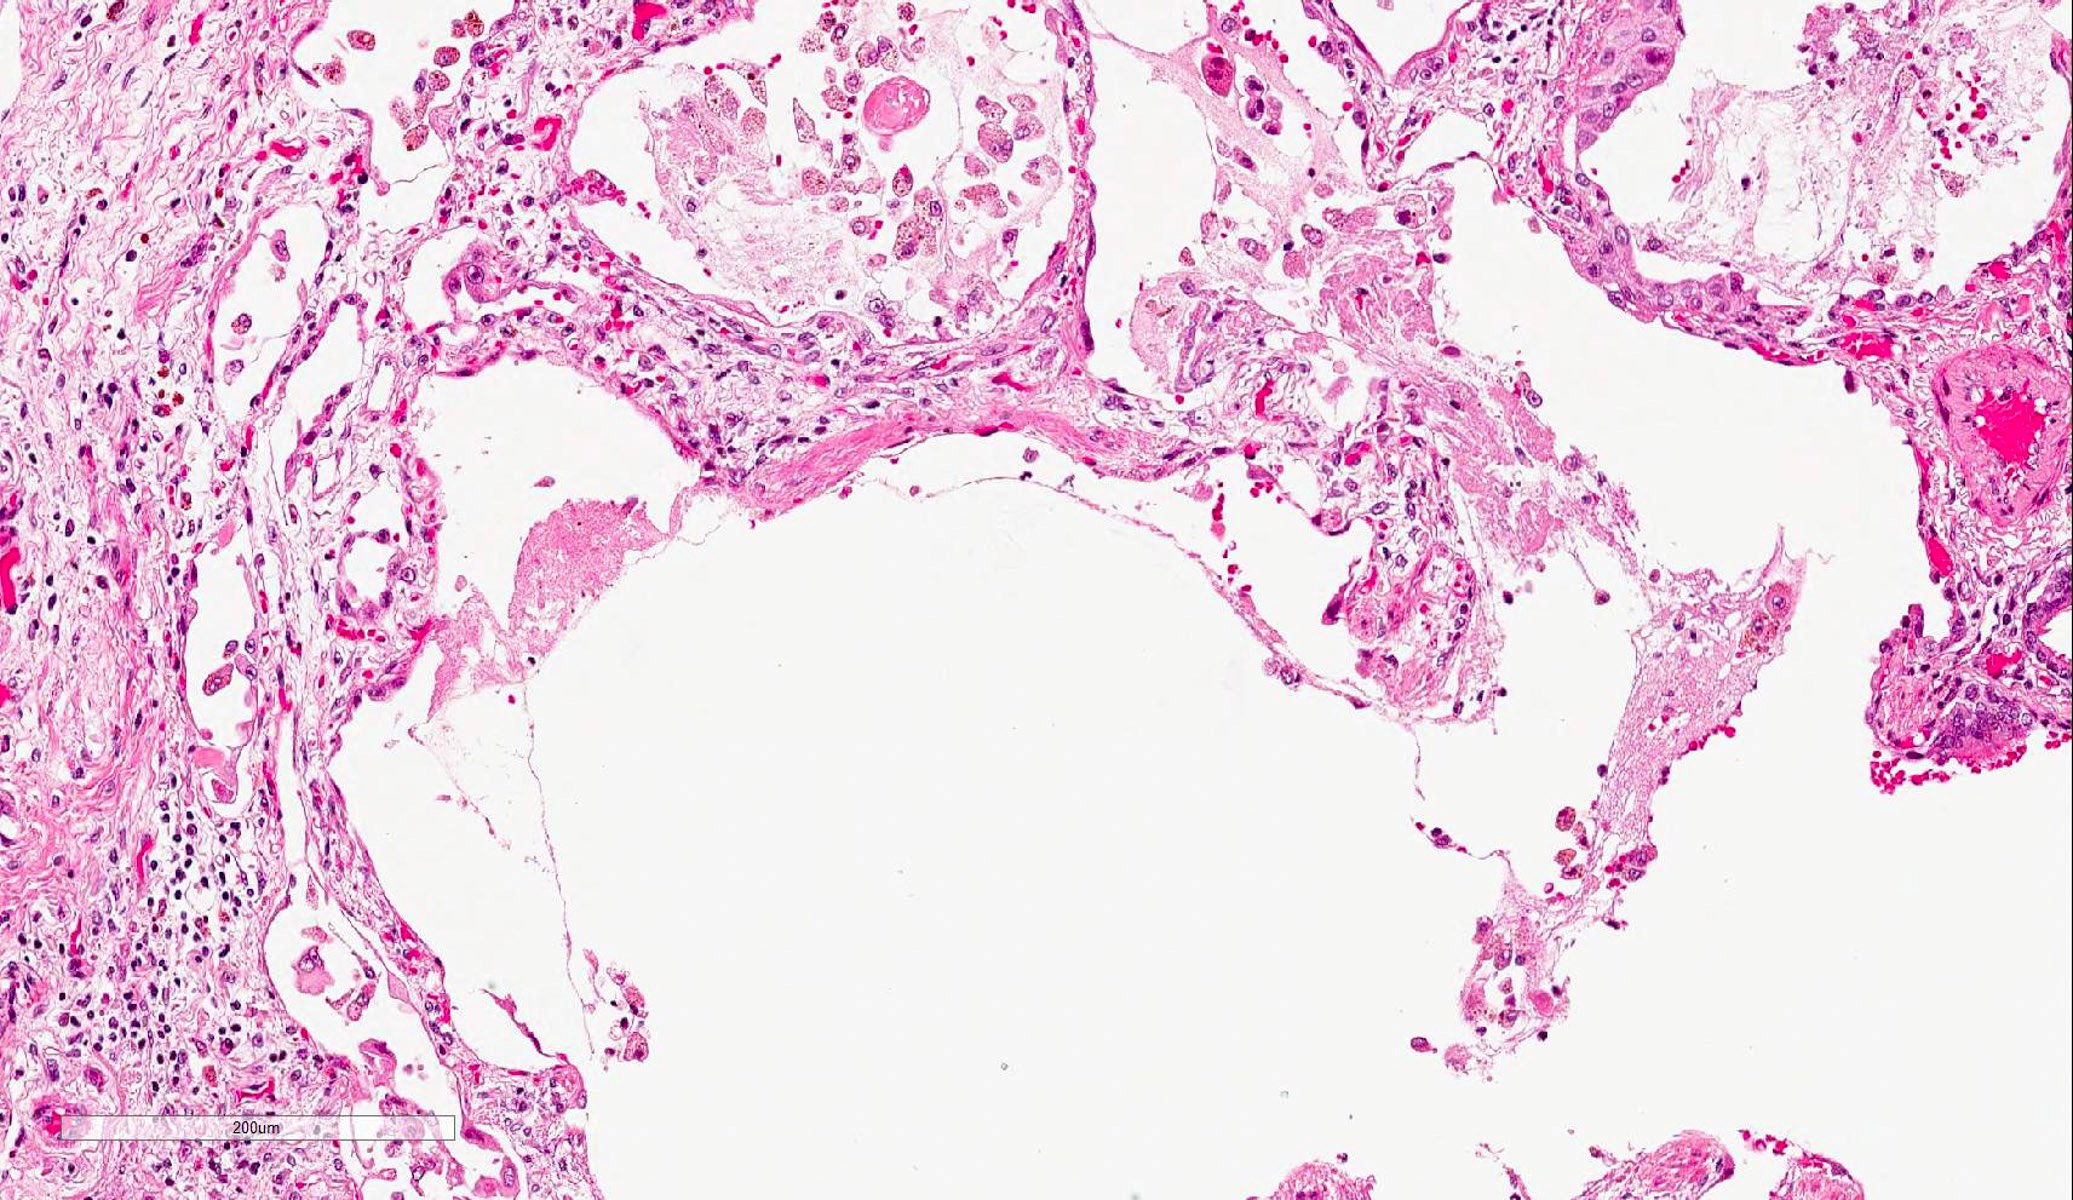

Microscopic (histologic) description

- Histopathology of DAD progresses from exudative (acute) phase through proliferative / organizing (subacute) phase to chronic fibrotic phase roughly corresponding to the period of ARDS (Am J Pathol 1976;85:209, Arch Pathol Lab Med 2010;134:719, Clin Chest Med 2000;21:435, N Engl J Med 2000;342:1334)

- Proliferative / organizing (subacute) phase

- Alveolar change

- Remnants of hyaline membrane with or without organization

- Interstitial and intra-alveolar proliferation of myofibroblasts

- Lymphocytic infiltration

- Epithelial change

- Proliferation / hyperplasia of type II pneumocytes

- Vascular change

- Endothelial injury and thromboemboli in arterioles

- Alveolar change

Microscopic (histologic) images

Contributed by Akira Yoshikawa, M.D. and Yale Rosen, M.D.